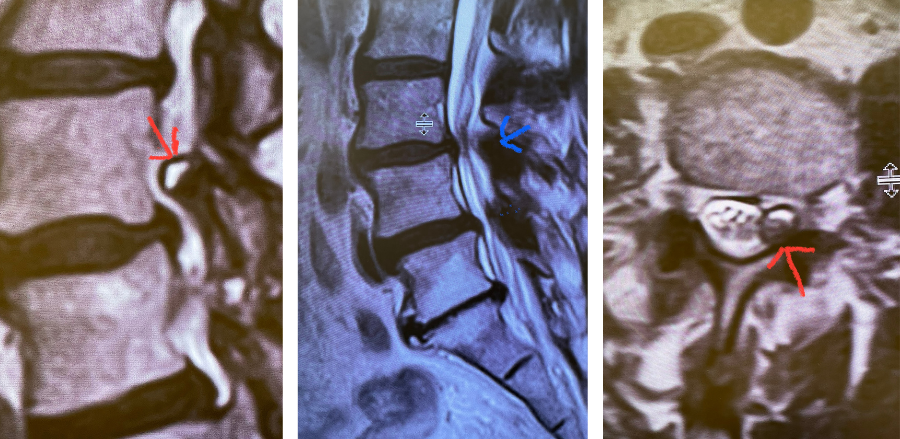

Fig 1: Sagittal and axial T2-weighted MRI images demonstrating a large superiority-oriented synovial cyst (red arrow) at L4-5. The cyst is below the exiting L4 nerve root and hence compresses the descending L5 root. Note the additional thickened ligamentum flavum and slight spondylolistheses at L3-4 and L4-5 (blue arrow).

This 63-year-old female presents with nine months of low back pain and pain radiating to the lower extremities with the left leg worse than the right. The patient complained of numbness and tingling as well. The pain was exacerbated by standing, walking, and coughing. An MRI demonstrated severe lumbar stenosis L3-L5 with a superimposed left L3-4 synovial cyst (Fig 1).

The patient also had a slight spondylolisthesis at L3-4 and L4-5. The patient failed all means of conservative management including medications, physical therapy, and epidural injections. The patient elected to proceed with a decompressive laminectomy and in-situ fusion. During the procedure we encountered a thick-walled cyst that melded with the dura. We first found the descending left L4 nerve root and separated the cyst and proceeded to in essence bite away the cyst with an instrument. We decompressed the L4 nerve root as it entered its foramina by removing the majority of the cyst wall. There was thick gray gelatinous material within the cyst. Part of the cyst wall seemed to be continuous with the dura and left it alone as it caused no pressure on the root. After our decompression we decided to perform an in-situ fusion as we had relative preservation of the joint complexes. Post operatively, she had an uneventful course with significant relief of her leg pain.